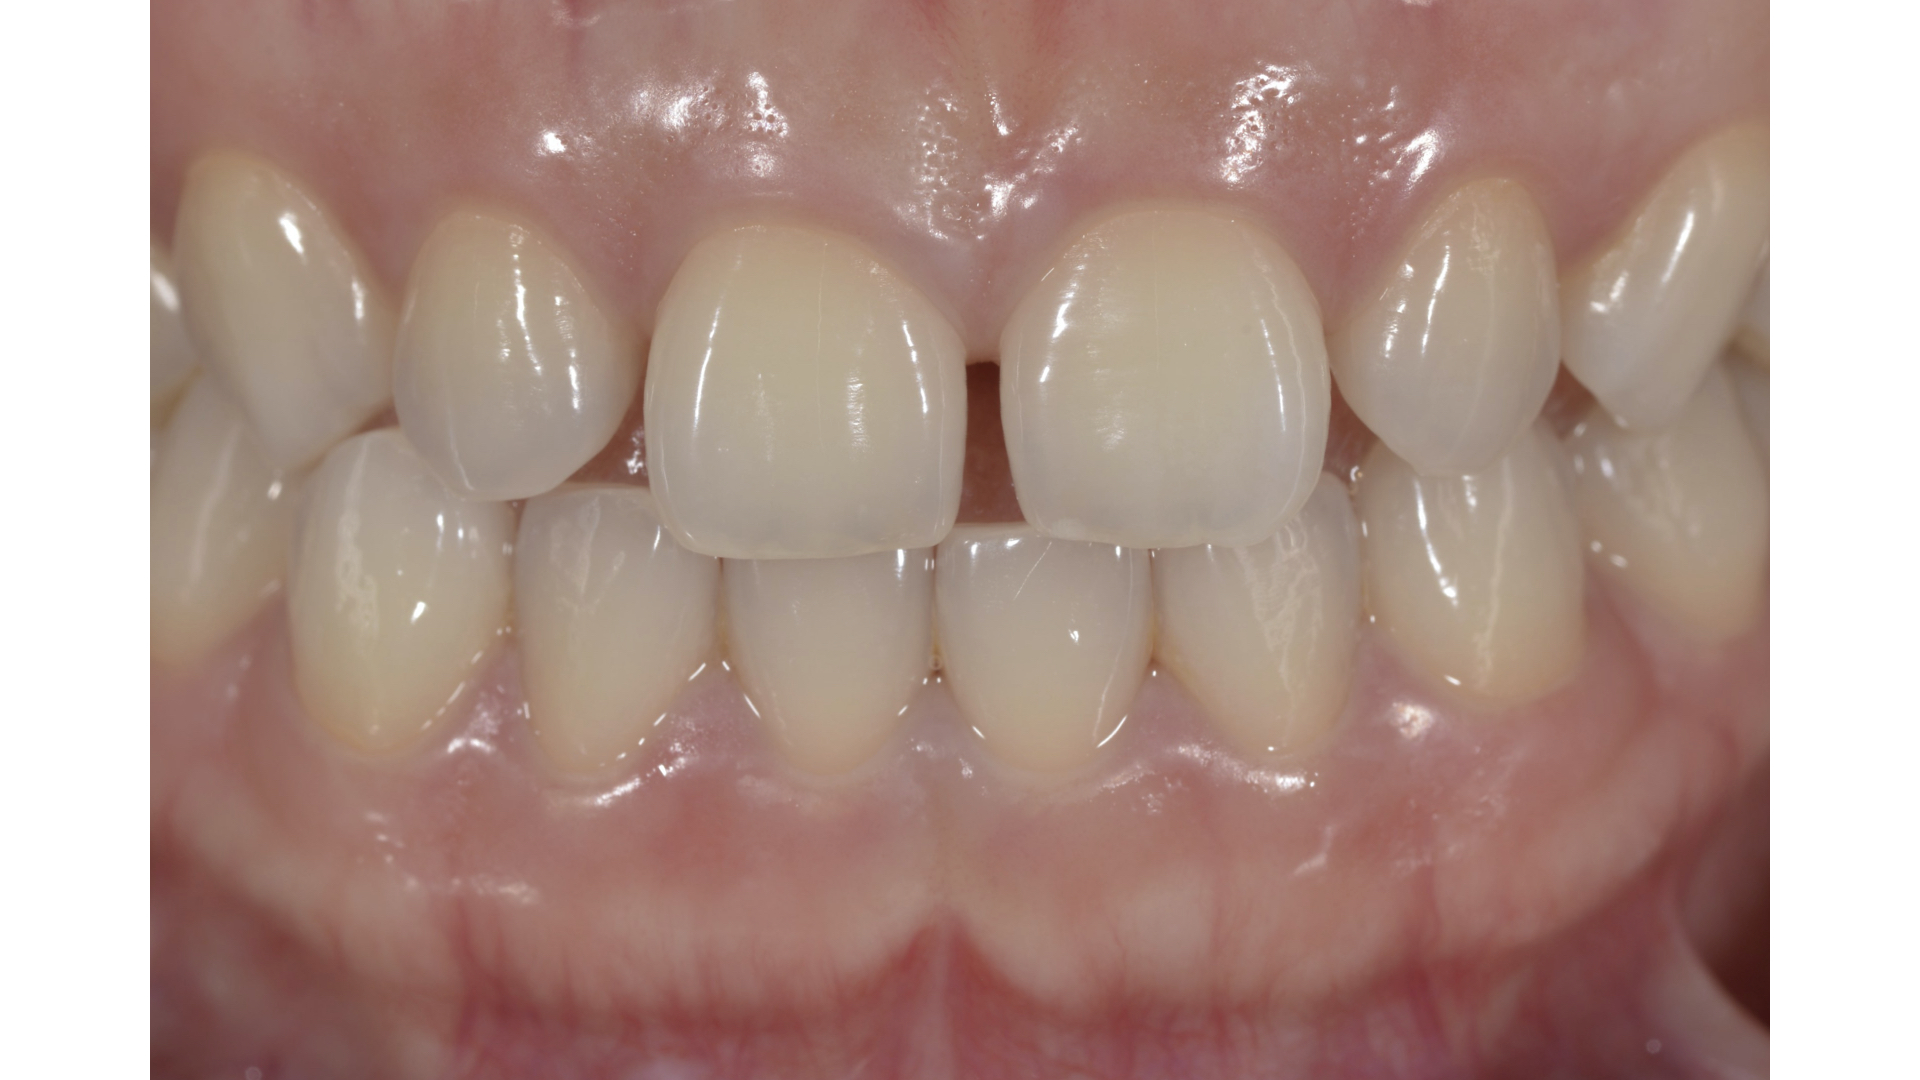

門牙中間有縫